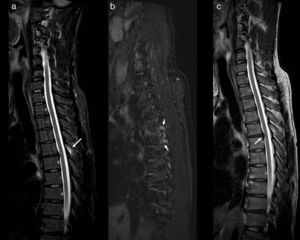

One important issue is that often the appropriate sequences are not carried out. In this regard, it has been reported that the STIR sequence is the most suitable for screening traumatic lesions in the rachis, since it saturates fat and boosts the signal in tissues with long relaxation times in T2, increasing sensitivity in the detection of bone marrow and soft tissue oedema. So much so that it has been singled out owing to its luminosity, in which lesions show up like light bulbs, being qualified as a “forensic sentinel sign”14 (Fig. 2). Numerous studies refer to the usefulness of this sequence as a way of screening in minor injuries,15–17 emphasising the value thereof for detecting lesions in ligaments which would otherwise go unnoticed.18 Consequently, one could say that an early MRI scan that does not include this sequence would be nothing short of invalid for forensic purposes, as acute lesions in soft tissue and ligaments may go unnoticed.

MRI of dorsal column with STIR sagittal sequences (a), Dixon T2FS (b) and T2 (c). Bone marrow oedema can be observed in the spinous process of D5 (arrow in a) and in the pedicles of D5 and D6 (arrows in b), without defining fracture lines. A central protrusion of the disc D5-D6 is shown (arrow in c).